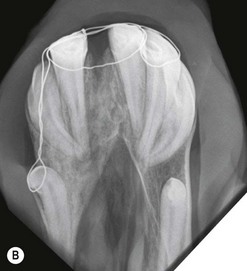

Intra-oral oblique projections (Figs 13.1913.20)

These projections, where a flexible film package or cassette is placed into the oral cavity, represent a modification of the bisecting angle technique used widely in human dental imaging. They have the advantages that there is no superimposition of structures from the contralateral side of the skull, and can also give good detail of the interdental bone and alveolar crest region. However, in the author’s experience, these projections can be difficult to obtain in standing sedated horses, due to difficulties keeping the film in place within the oral cavity.

image

Fig. 13.19 Diagram showing intra-oral position of the cassette and angles of incidence of the X-ray beam to obtain intra-oral cheek teeth radiographs of young horses with long reserve crowns (left) and older horses (right).

Fig. 13.20 (A) Intra-oral radiograph of a maxillary cheek teeth row.

Radiograph courtesy of J. Easley.

(B) Intra-oral radiograph taken intra-operatively during a dental extraction procedure. A small bone-opacity fragment can be seen in the rostral aspect of the alveolus (arrow).

(Radiograph courtesy of W.H. Tremaine.)